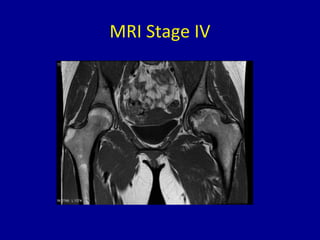

MRI Stage IV

Stage IV

• Flattening or collapse of head on x-ray

• Loss of joint space

• Subclassified by extent of collapse like Stage III